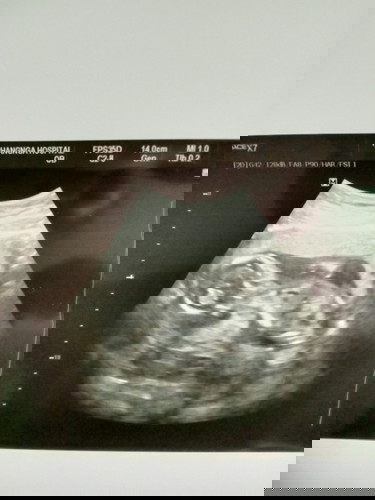

อายุครรภ์ 16w5

วันนี้คุณหมอนัด ได้ซาวด์ คุณหมอว่าน่าจะผู้ชาย ดีใจมากๆๆค่ะ อายุครรภ์ 16w5